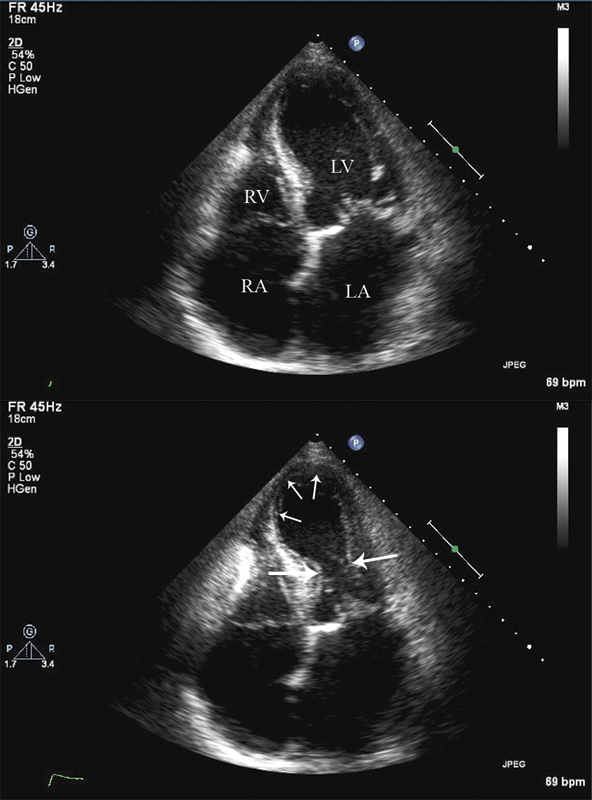

فحوصات تشخيصية لبعض امراض القلب والشرايين التاجية